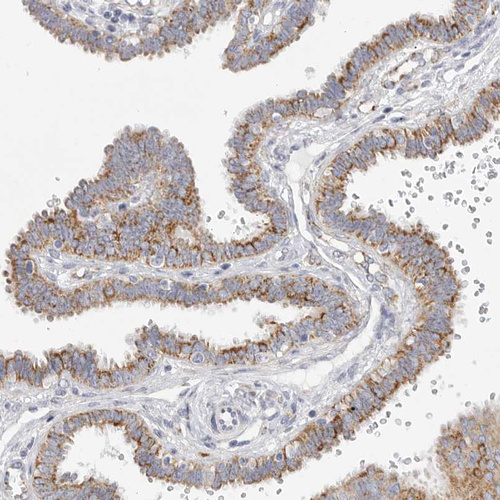

Immunohistochemical staining of human fallopian tube shows moderate cytoplasmic positivity in glandular cells.